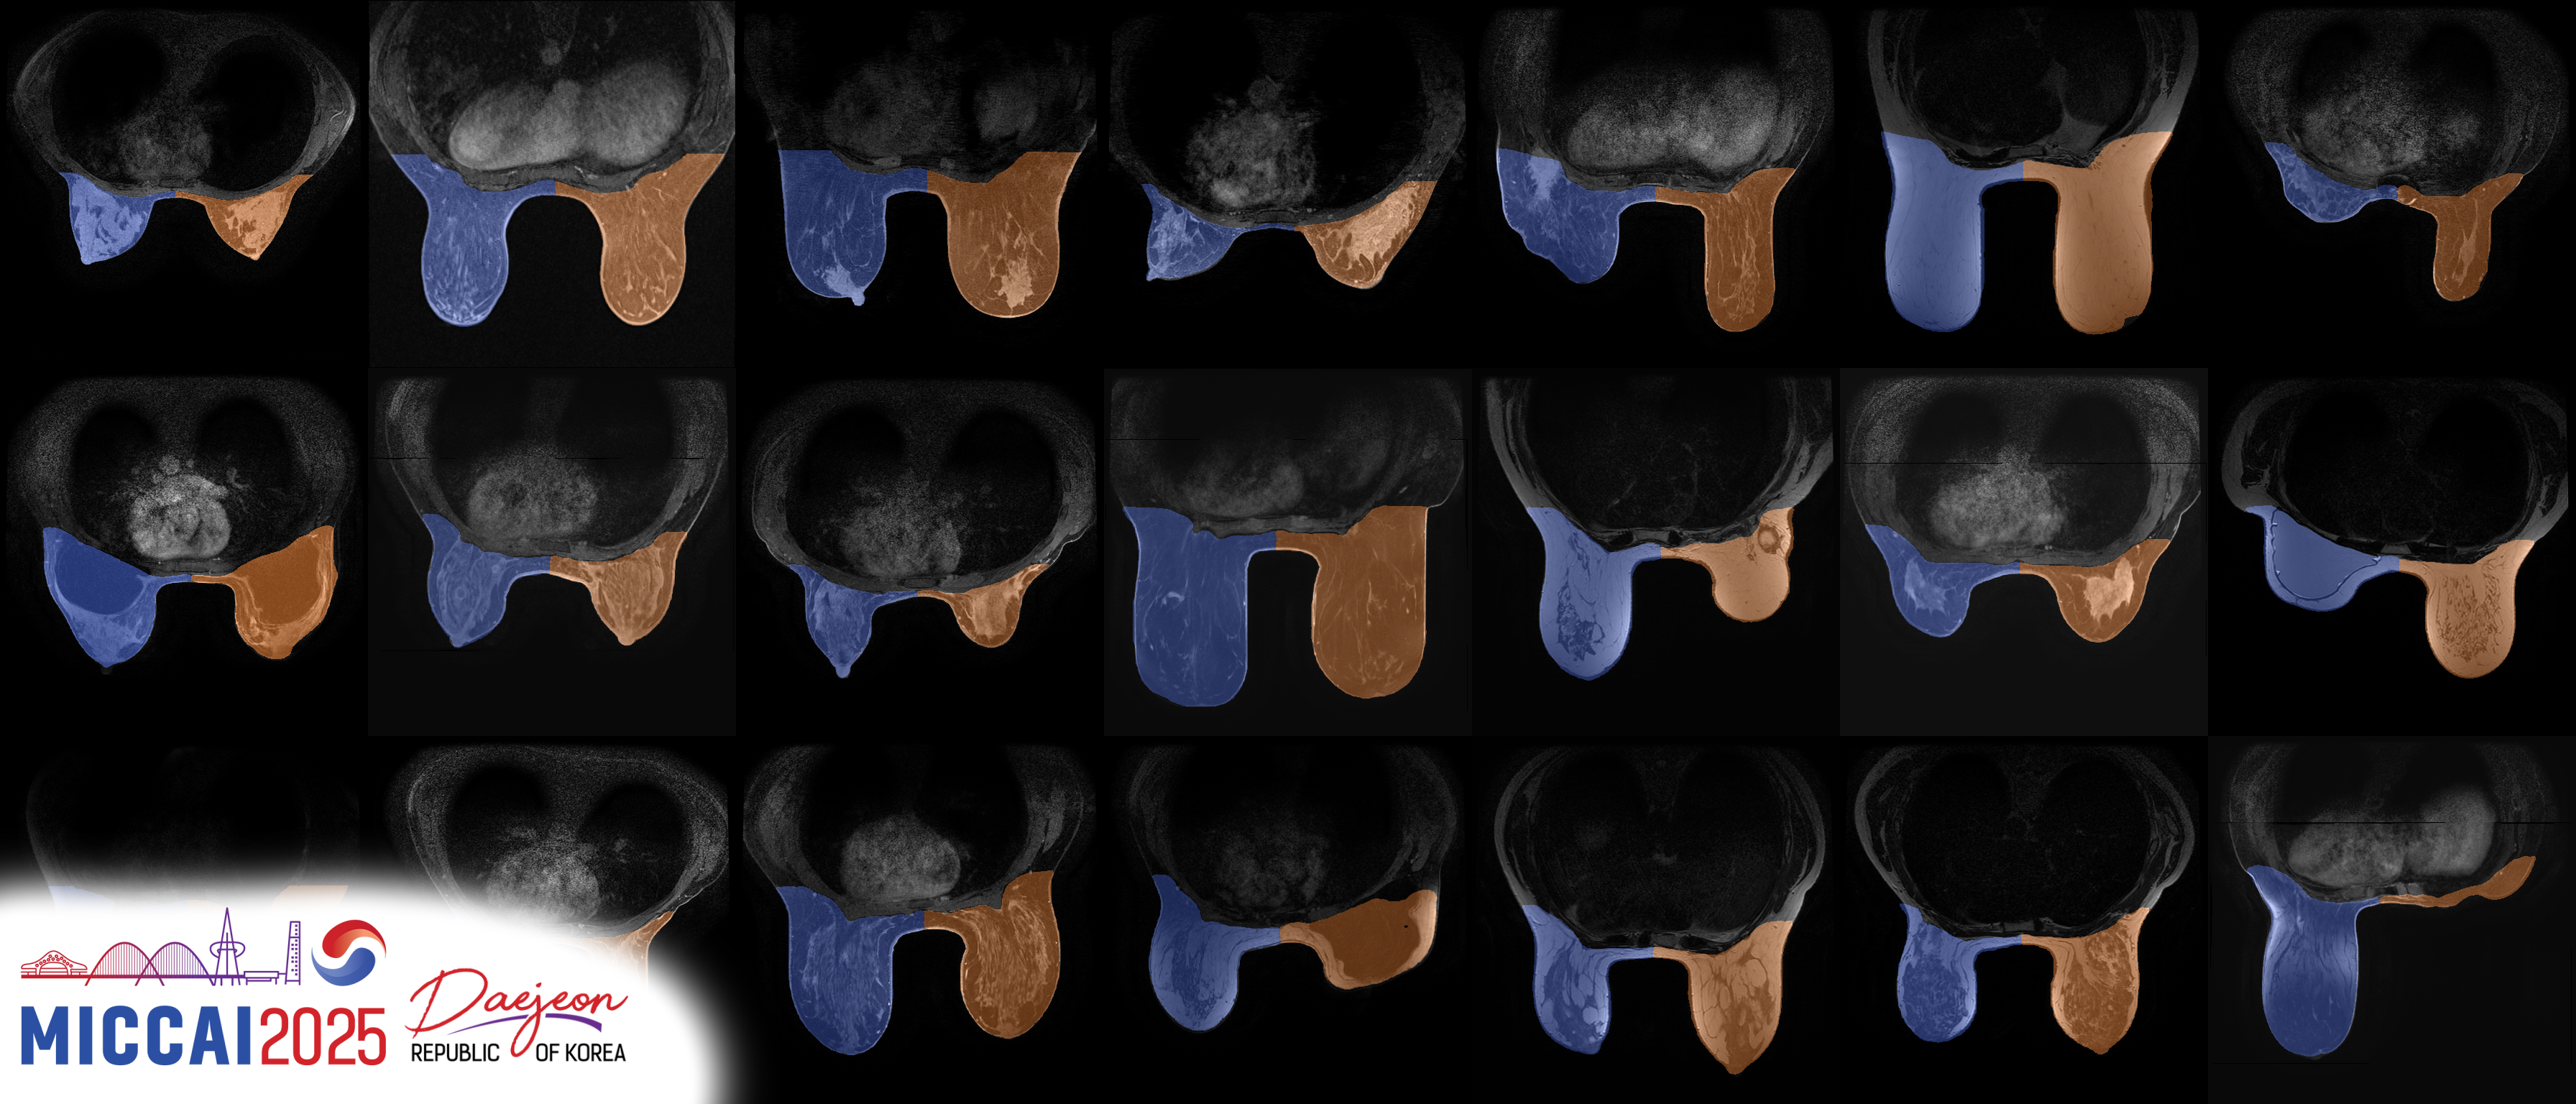

Breast MRI plays a pivotal role in breast cancer detection, diagnosis, and treatment planning. BreastDivider addresses a critical limitation in breast MRI segmentation: the lack of distinction between the left and right breasts in most public datasets and models.

In this work, we introduce the first publicly available large-scale dataset with explicit left and right breast segmentation labels, comprising over 13,000 3D MRI scans. Accompanying this dataset is a robust nnU-Net–based segmentation model, trained specifically to identify and separate left and right breast regions in clinical MRI data. This effort provides a foundation for developing high-quality, anatomically aware tools for breast MRI analysis and offers opportunities for large-scale pretraining.

The model is based on the nnU-Net framework and was trained on the full BreastDivider dataset, using a custom configuration that allows both breasts to fit into a single 3D patch.

It generalizes well across a variety of MRI modalities, including: